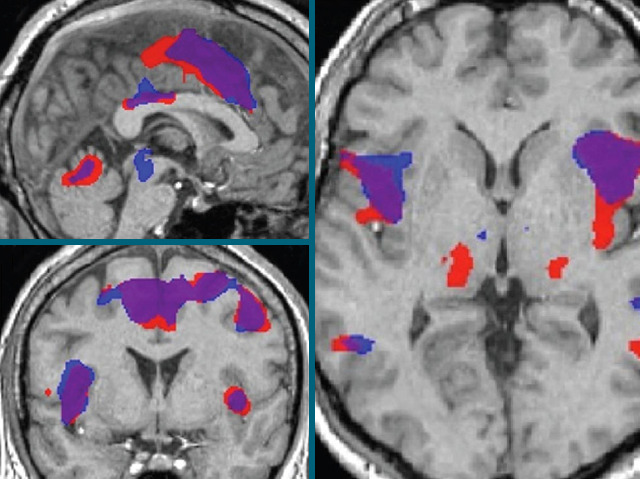

Red hot chilli peppers are a must for curry connoisseurs, but leave the mouth burning and eyes watering. The active ingredient is capsaicin that triggers pain receptors in the mouth and skin, sending electrical signals to the brain that register as pain. People with neuropathic pain experience the same prickly burning pain, incessantly. Neuropathic pain has no obvious cause, but is a common side-effect of nerve damage and can cause hypersensitivity to other pain stimuli such as heat. Here, MRI scans of the side (top left), back (bottom left) and top (right) of the head show which brain areas become activated when a heat stimulus is applied to the arm. Heat alone activates areas marked blue, but when capsaicin is first applied briefly to the skin, activation spreads into the red (overlapping areas, purple). Capsaicin-induced pain could provide a new model to test novel pain-killers for neuropathic pain.